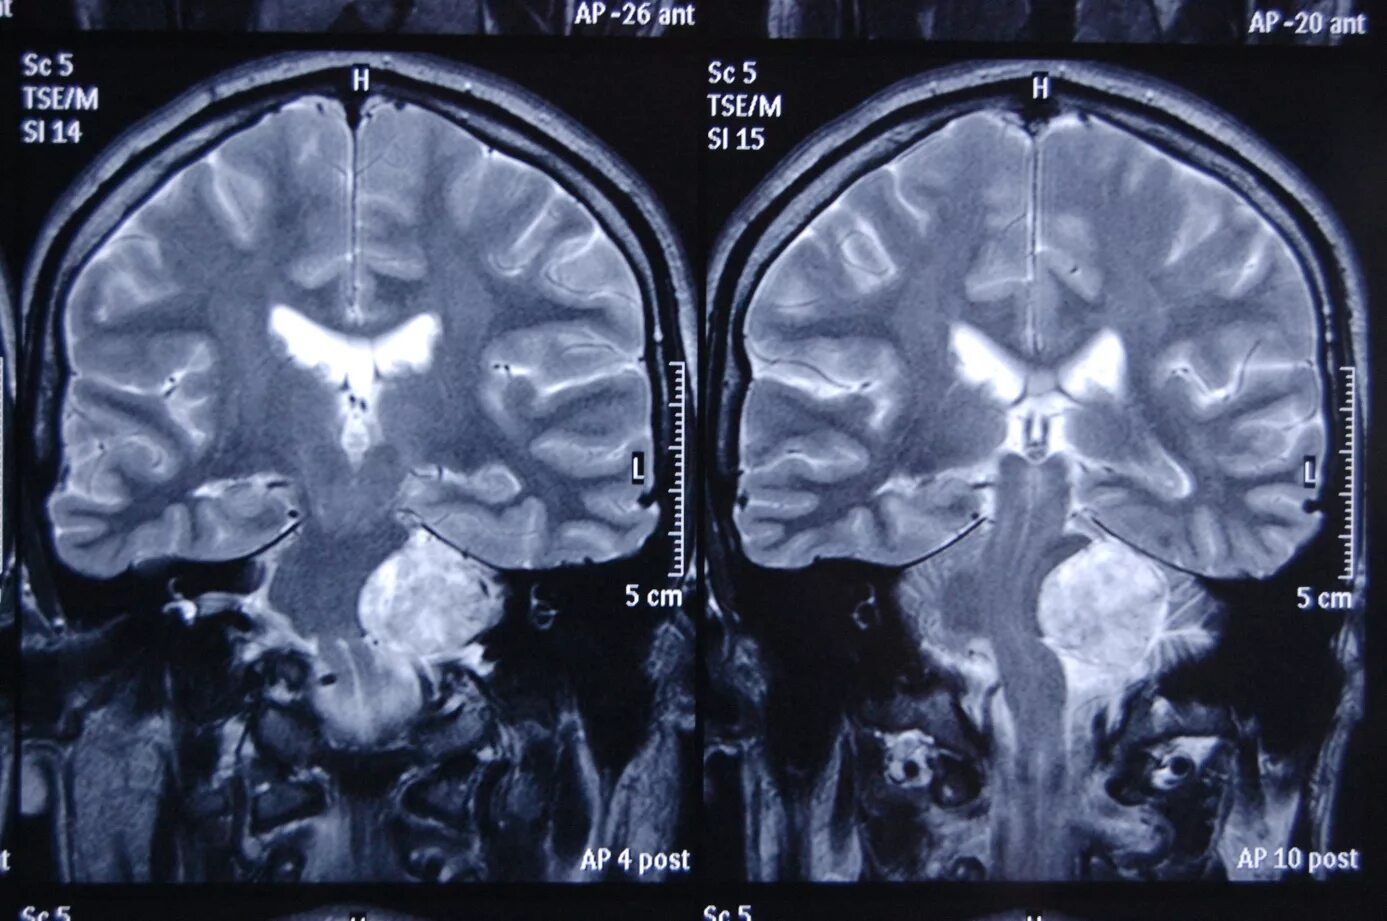

Мрт головного мозга мосто мозжечкового угла